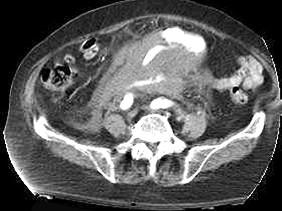

问题 关于腹主动脉瘤,下列哪项是正确的 ( )

选项 A、外科手术是根治腹主动脉瘤的唯一方法 B、CT能够更准确地显示瘤体的三维形态体征 C、腹主动脉瘤病人出现腹痛或腰背痛时意味着动脉瘤破裂 D、MRI在造影剂的帮助下可以充分显示瘤体的大小 E、直径2cm以上的动脉瘤可以用超声多普勒检查出来

答案 C